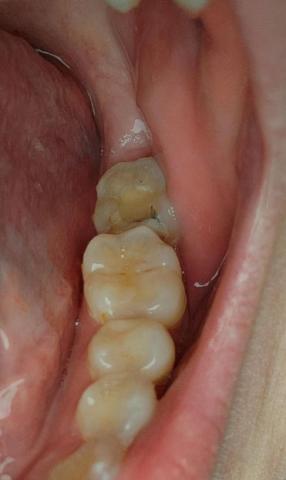

Case Overview (100% Zoom Visual Inspection)

The image shows posterior molars/premolars with visible occlusal surface discoloration, dark pits, and irregular enamel texture. One tooth presents brown-black staining within fissures, strongly suggestive of active dental caries or recurrent decay under an old restoration.

Tooth-by-Tooth Visual Assessment

Tooth 1 (Most Posterior Visible)

Dark fissure staining

Loss of natural enamel translucency

Possible early cavitation

High plaque retention area

Tooth 2 (Middle Molar)

Yellow-brown occlusal discoloration

Surface wear and staining

Early enamel demineralization suspected

Tooth 3 (Anterior Premolar)

Mild staining

Enamel largely intact

Lower immediate risk

Clinical Diagnosis (Visual-Based)

Primary diagnosis: Occlusal dental caries

Secondary concern: Enamel demineralization

Risk of progression to dentin involvement

Possible microleakage if an old filling exists